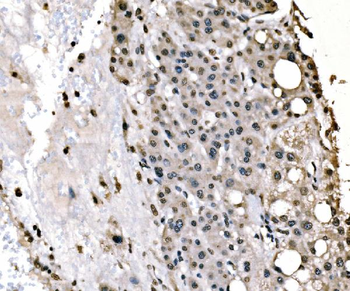

100 μl, 50 μl, 200 μl - ATF4 Recombinant Rabbit Monoclonal Antibody [orb704304]Featured

FC, ICC, IF, IHC-Fr, IHC-P, WB

Human

Mouse

Rabbit

Recombinant

Unconjugated

50 μl, 100 μl - MARK3 Recombinant Rabbit Monoclonal Antibody [orb704310]Featured